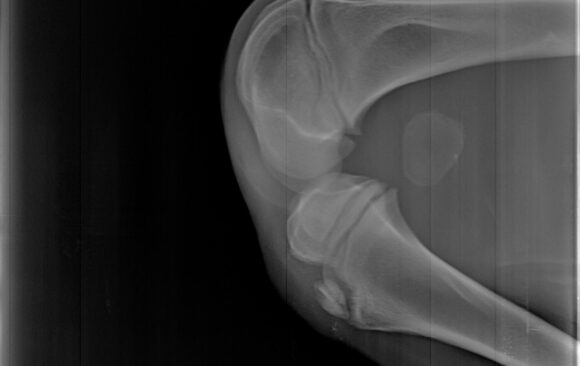

Dan za pregled

Malena Stana je mirna i puna poverenja ležala tokom pregleda, puštajući da je namestimo kako je za snimanje rendgenom bilo...